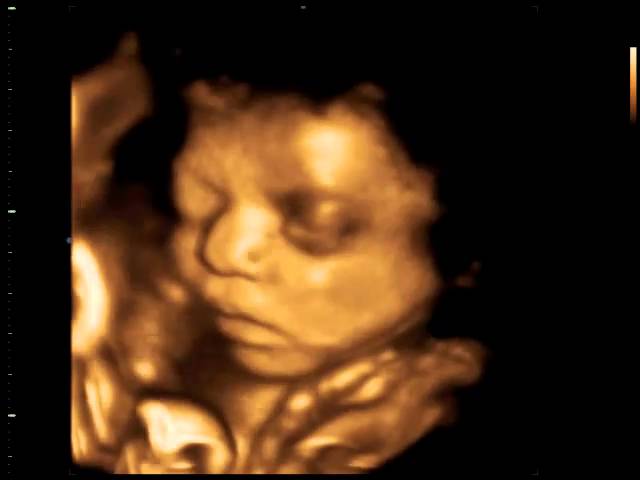

Ambas mostram detalhes do bebê, tais como contornos e fisionomias. A 4D permite ver o bebê em movimento, sorrindo, bocejando, passando a mão no rosto, abrindo e fechando as mãos entre outras peripécias.

Atualmente, disponibilizamos de tecnologia capaz de oferecer imagens tão reais dos bebês que podemos dizer com quem eles se parecem mesmo antes de nascerem. Podemos acompanhar com detalhes cada passo da formação de uma nova vida.